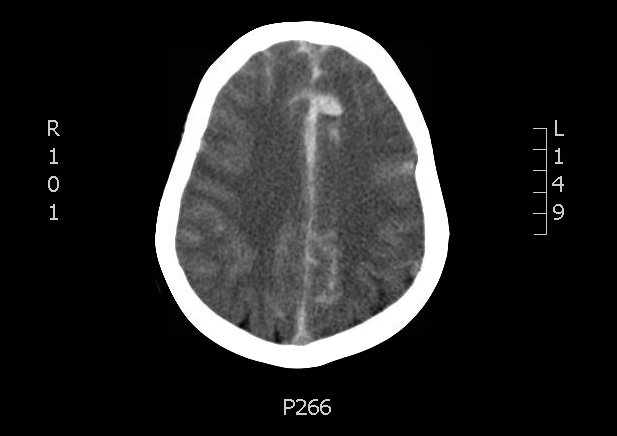

A non-contrast head CT demonstrated extensive subarachnoid hemorrhage occupying both cerebral convexities, the anterior interhemispheric fissure, the sylvian fissures, and the basal cisterns. Later CTA would show an 8 mm by 7 mm by 8mm MCA aneurysm near the M1/M2 junction and two pericallosal artery aneurysms, 7 by 6 mm and 8 by 5 mm respectively.

The patient underwent external ventricular drain (EVD) placement by neurosurgery, followed by coiling of the three aneurysms by interventional radiology.